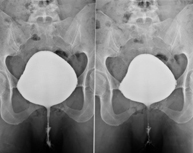

La urografia intravenosa (UIV) consisteix en l'obtenció d'imatges radiològiques seriades del ronyó, vies urinàries i bufeta. Aquest estudi requereix sempre l'ús d'un contrast iodat. - Cistografía (CUMS)

La cistouerotrografia miccional seriada consisteix en l'obtenció d'imatges radiològiques per valorar l'anatomia i la funció de la uretra i la bufeta amb l'administració de contrast iodat a través d'una sonda vesical. - Uretrocistografia (Uretro-Cums)

La uretrocistrografia retrògrada i miccional consisteix en l'obtenció d'imatges radiològiques per valorar l'anatomia i la funció de la bufeta i de la uretra. S'aplica material de contrast a través d'una petita sonda que es troba a la uretra i s'obtenen imatges durant l'ompliment i el buidatge de la bufeta. - Pielografia ascendent per catèter

- Cystography

Serial voiding cystourethrography involves radiological imaging to assess the anatomy and function of the urethra and bladder with the administration of iodinated contrast through a bladder catheter.